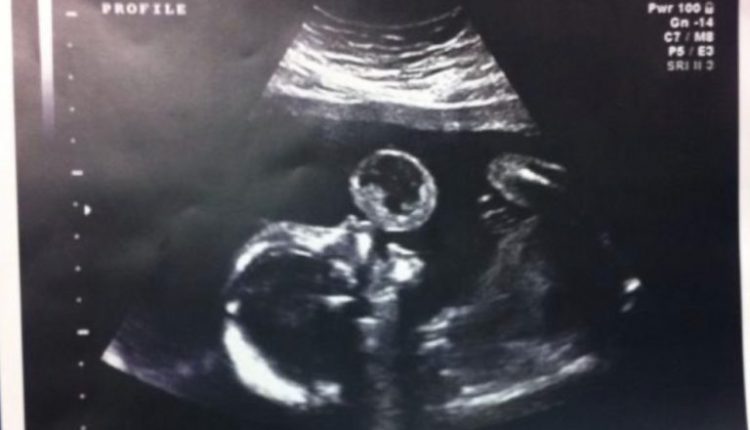

Коли 39-річна Таммі Гонзалес вирушила на чергове обстеження під час вагітності, вона абсолютно не була готова до того, що побачить під час УЗД. На екрані мама побачила біля рота дитини щось схоже на величезну бульку.

Лікарі провели аналізи і повідомили майбутній мамі погані новини: тератома — пухлина, яка росте з клітин ембріона. Це досить рідкісне явище — один випадок на 100,000. Лікарі сказали, що через пухлину в роті дитина, швидше за все, помре. А навіть якщо і виживе, то після народження потрібно буде перенести безліч операцій. Виходячи з цього, лікарі порадили жінці перервати вагітність.